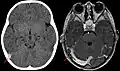

Тромбоз синусов твёрдой мозговой оболочки — редкая форма нарушения мозгового кровообращения, представляющая собой ухудшение оттока крови от головного мозга из-за закупорки синусов кровяными сгустками (тромбами). Проявляется головной болью, нарушением зрения, гемипарезом лица или конечностей, судорогами и др. Диагноз устанавливается на основе данных компьютерной или магнитно-резонансной томографии с внутривенным контрастным усилением, позволяющих визуализировать обструкцию венозных синусов тромбом.[1] Для лечения применяется терапия антикоагулянтами, реже — тромболитиками. Так как данная патология обычно является осложнением другого заболевания, может потребоваться дополнительное обследование. Тромбоз венозных синусов может осложниться внутричерепной гипертензией, для купирования которой в некоторых случаях применяется хирургическое вмешательство (например, шунтирование).[1]

Синус-тромбоз при нативной компьютерной томографии (слева) и МРТ в режиме T1 с контрастным усилением (справа)